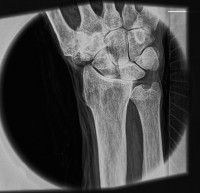

| Снимок запястья, демонстрирующий способность системы «видеть» мягкие ткани. Источник: Luis Velásquez-García et al. |

Рентгеновские аппараты не дают возможности получать снимки мягких тканей без контрастных агентов наподобие бария, и разрешение таких снимков невелико. Разработка специалистов Массачусетского технологического института и Массачусетской больницы общего профиля обещает кардинальные перемены: гораздо более детальные снимки, в том числе мягких тканей, без контрастных агентов. К тому же аппарат из МТИ компактнее традиционных и выдает меньшую дозу облучения.

Вместо традиционного одиночного источника большой мощности в новом аппарате используется матрица микроисточников, испускающих когерентный пучок рентгеновских лучей. Такую матрицу исследователи изоготовили, воспользовавшись технологиями, применяемыми в полупроводниковом производстве. По оценкам разработчиков, система позволит получать снимки с разрешением в сотню раз больше, чем обычно, а стоить будет на порядки меньше, чем традиционные аппараты.